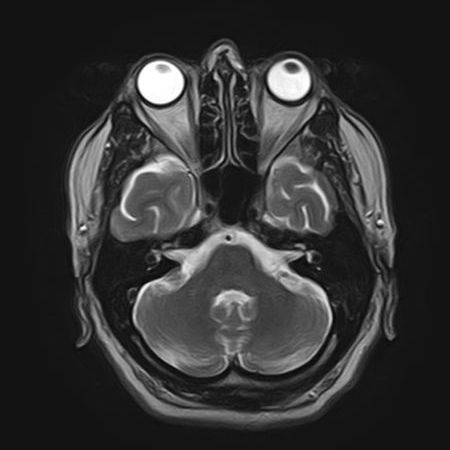

MRT

Magnetresonanztomographie (MRT)